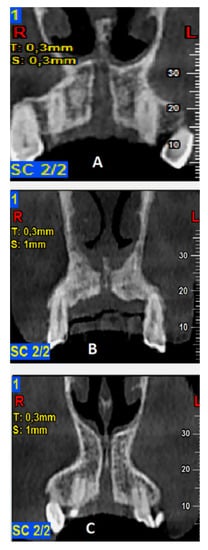

Figure 3.

Classification of anatomic types of the nasopalatine canal (NPC) as evaluated in coronal cone beam computed tomography (CBCT) images: (A)—a single canal, (B)—two parallel canals, (C)—variations of the Y-type of canal with one incisive foramen (IF) and two or more Stenson foramen (SF).

Evaluation of the different anatomic types of NPC resulted in the detection of a single canal in 56.5%, two separate parallel canals in 25%, and variations of the Y-type canal in 18.5% of the scans, respectively (Figure 3). The descriptive analysis of NPC dimensional evaluation parameters is presented in Table 1.